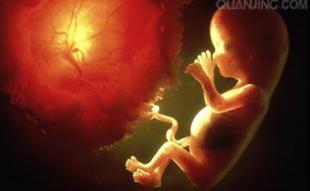

胎儿最初的50天长成啥样?

孕妈烟不离手,胎儿在四维彩超中的模样,让

50天胎儿发育图片欣赏